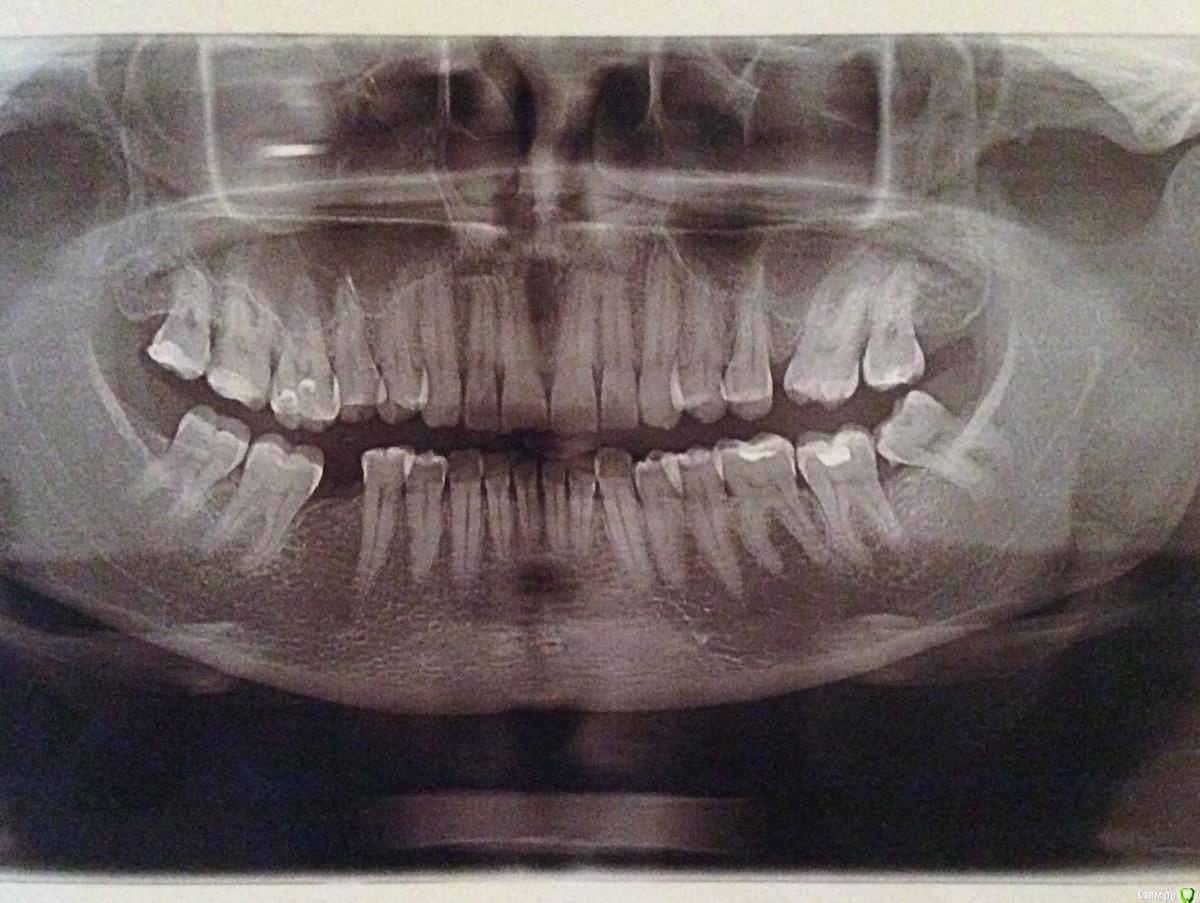

DmitrySH Опубликовано 12 мая, 2016 Поделиться Опубликовано 12 мая, 2016 (изменено) Сможете выложить срез КТ где этот "мертвый" зуб?На панорамном снимке ничего подобного не вижу Изменено 12 мая, 2016 пользователем DmitrySH 1 1 Ссылка на комментарий

Julsvs Опубликовано 13 мая, 2016 Автор Поделиться Опубликовано 13 мая, 2016 Вот КТ( проблема в правой шестерке). Другого снимка нет- выдали результаты на диске. Ссылка на комментарий

Doctor Vlad Опубликовано 13 мая, 2016 Поделиться Опубликовано 13 мая, 2016 это снова опг получилось. окно в программе наведите на 16 15 зубы и срезы тоже выложите 1 Ссылка на комментарий

DmitrySH Опубликовано 13 мая, 2016 Поделиться Опубликовано 13 мая, 2016 Мелковат снимок. Да, там есть изменения вокруг шестерки. Может на КТ там что-то еще можно увидеть. Но если судить по этому снимку, то зуб подлежит эндодонтическому лечению. Для удаления сейчас нет поводов. 1 Ссылка на комментарий